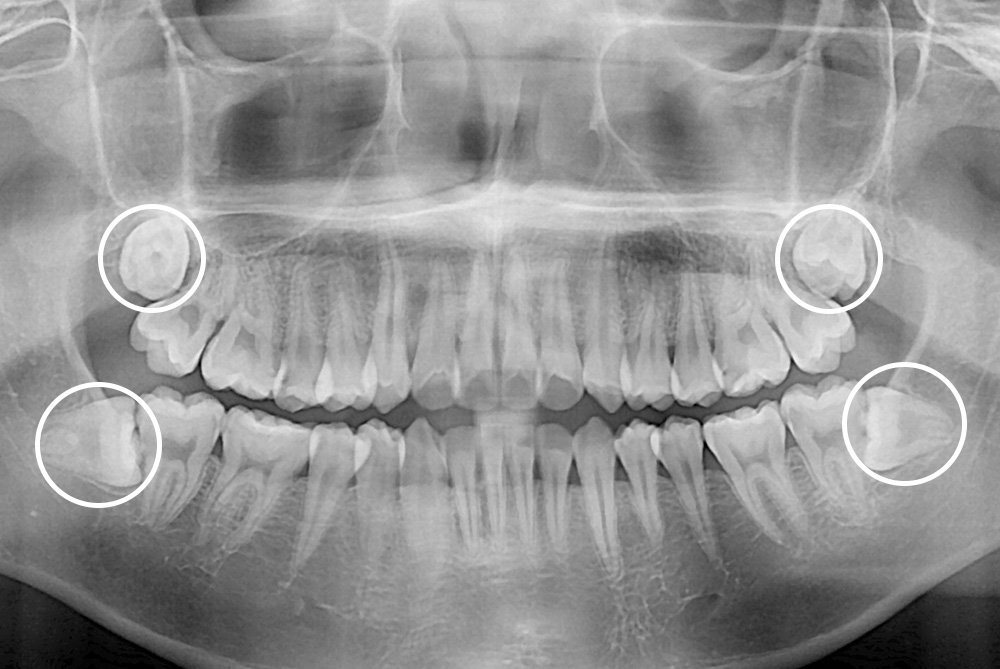

[사랑니] 매복 사랑니 발치

치료전 : 2018-10-16